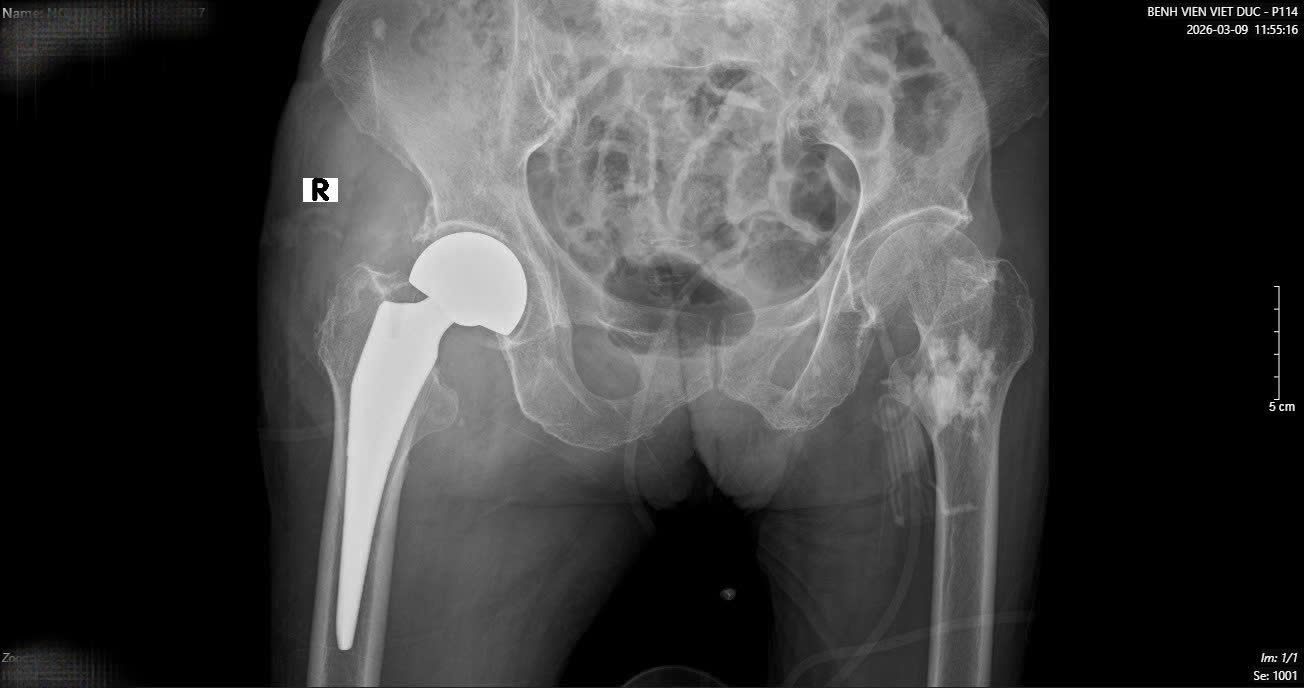

Hình ảnh phim X-quang cụ bà 89 tuổi nhập viện gãy cổ xương đùi phải và hình ảnh chụp CT ổ bụng và phát hiện khối u ruột non gây lồng ruột.

Sau một tuần, khi các chỉ số sức khỏe ổn định, cụ bà tiếp tục bước vào cuộc đại phẫu thứ hai. TS.BS Hoàng Ngọc Sơn đã trực tiếp phẫu thuật thay khớp háng cho cụ. Nhờ sự chuẩn bị kỹ lưỡng của đội ngũ y bác sĩ, ca mổ đã thành công tốt đẹp.